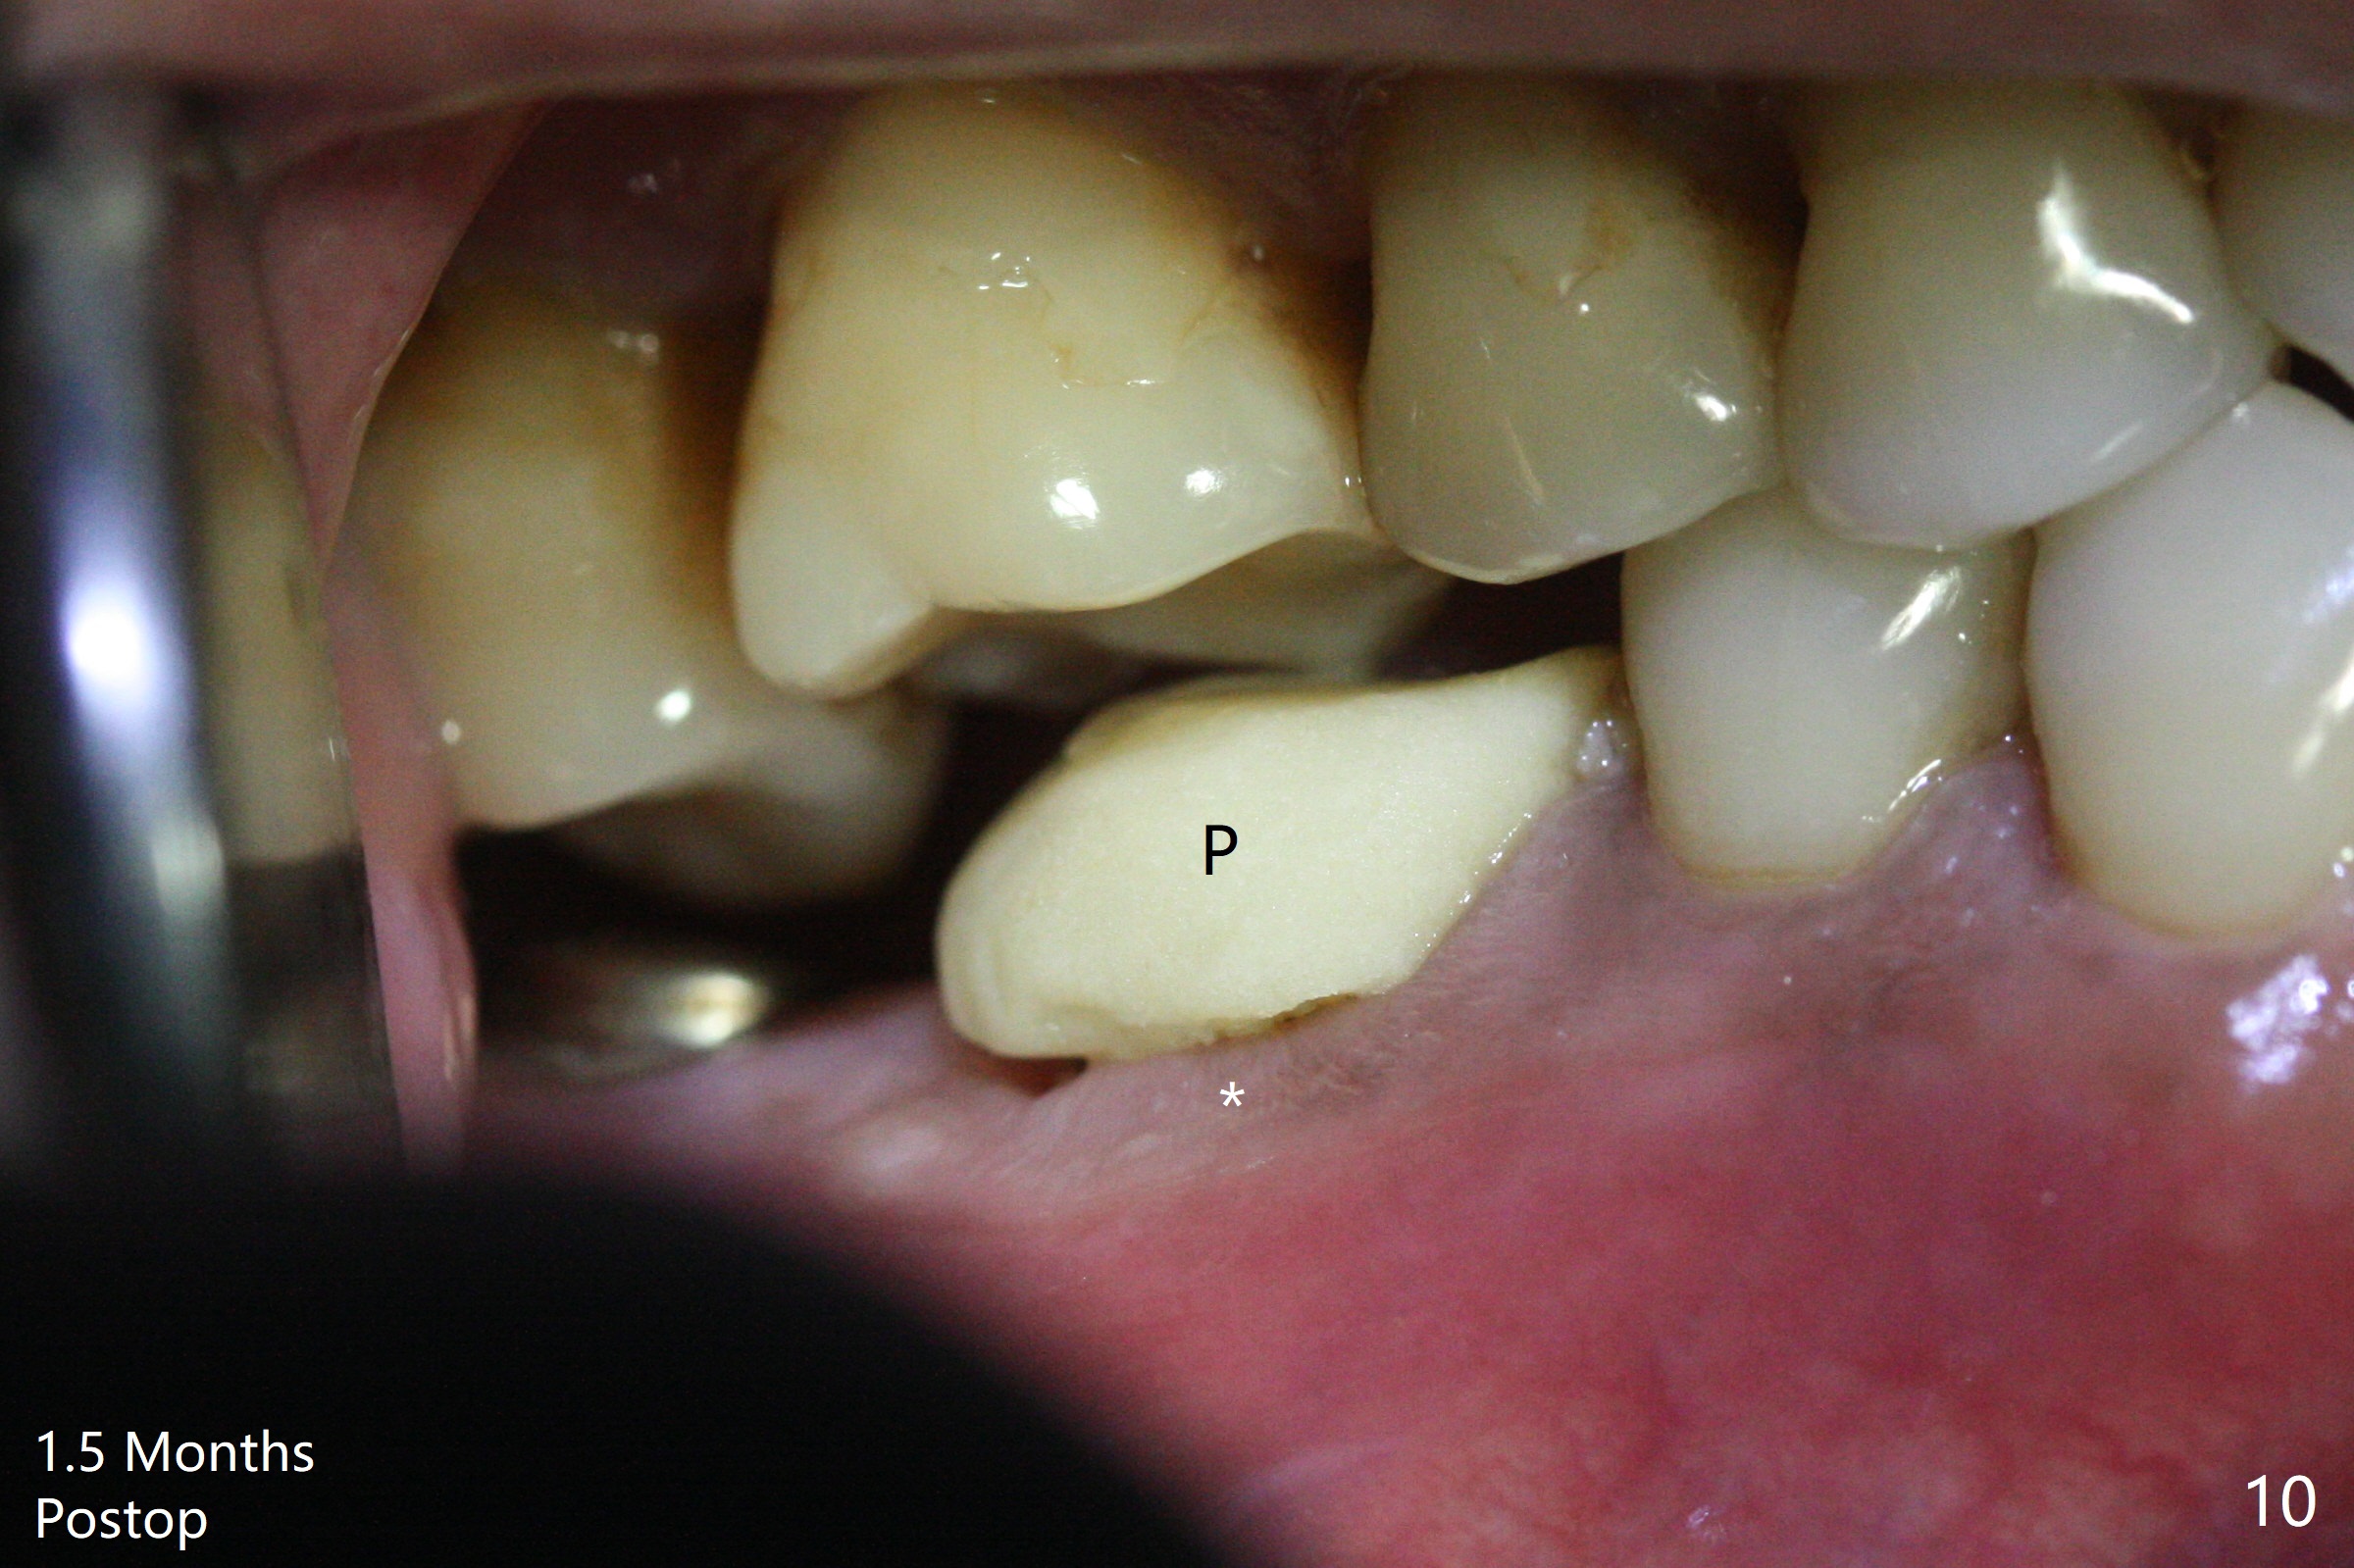

Abutment vs. Definitive One

After extraction of the tooth #30 with lingual subgingival fracture (Fig.1), the septum is fairly large (Fig.2 S). A bony vertical anchor pin (Fig.3 *) is inserted in the septum following pointed drill to to stabilize the guide during osteotomy and implant placement of #31. When the latter is finished, a fixture anchor pin is used at #31 as planned. A healing abutment is placed at #31 because of supraeruption of the tooth #2 (Fig.4,5), while a cementation abutment is placed at #30 (Fig.5) with autogenous bone (from drills) and allograft placed around it (*, Fig.6). Finally an immediate nonfunctional provisional is fabricated to keep the bone graft in place (Fig.7 P). The bone graft remains in place gel-like nearly 1 month postop (Fig.8). CBCT axial section shows that there is not enough space for mini implant placement at the tooth #2 (Fig.9). Restoration-induced intrusion will be conducted using the implants at #30 and 31 three-4 months postop. The buccal gingiva (Fig.10 *) is lingual to the provisional (P) nearly 1.5 months postop. When the provisional is removed, it appears that the mesiobuccal bone graft has lost (Fig.11). Two days later, the cementation abutment is loose and removed; the gingival cuff looks healthy (Fig.12). A 6.8x5 mm healing abutment is placed (Fig.13). In 2.5 to 3 months, abutments will be placed at #30 and 31. Splinted provisional will be fabricated over supraocclusion to intrude the tooth #2 with a stop on the left side. Surprisingly the patient agrees to intrude the tooth #2 with 2 mini implants 5.5 months postop (Fig.14,15). However, the miniimplants dislodged. Due to coronavirus, the implants are restored with heavy abutment and opposing tooth trimming 1 year 9 months postop (Fig.16). Magicore should have been placed instead.